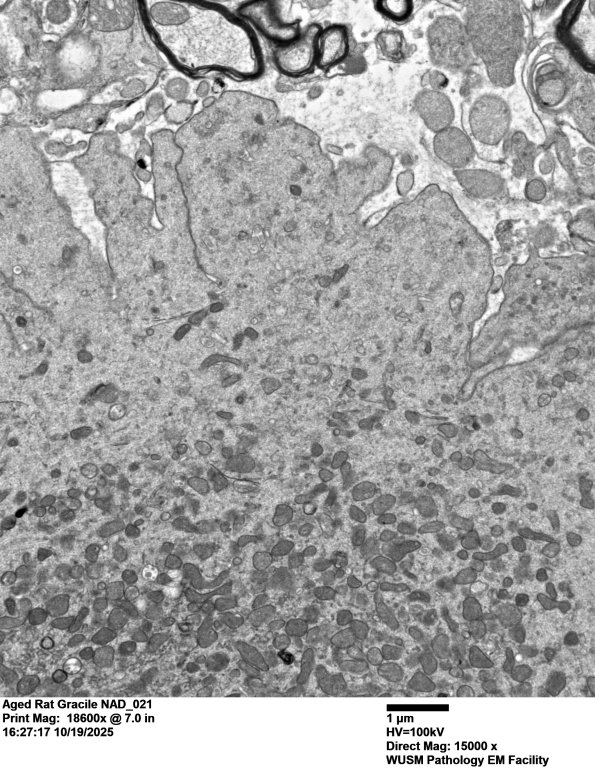

Note the unusual fluted margin of the dystrophic axon which is not spherical as are typical axonal spheroids. (electron micrograph)